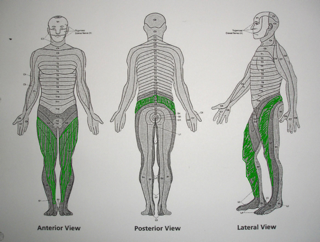

Θεραπεία συνδρόμου χρόνιας έντονης οσφυοισχιαλγίας, Που προκλήθηκε από προηγούμενες αποτυχημένες επεμβάσεις (failed back surgery syndrome), με επισκληρίδιο ηλεκτρική διέγερση νωτιαίου μυελού (τεχνική νευροτροποποίησης) σε γυναίκα 67 ετών